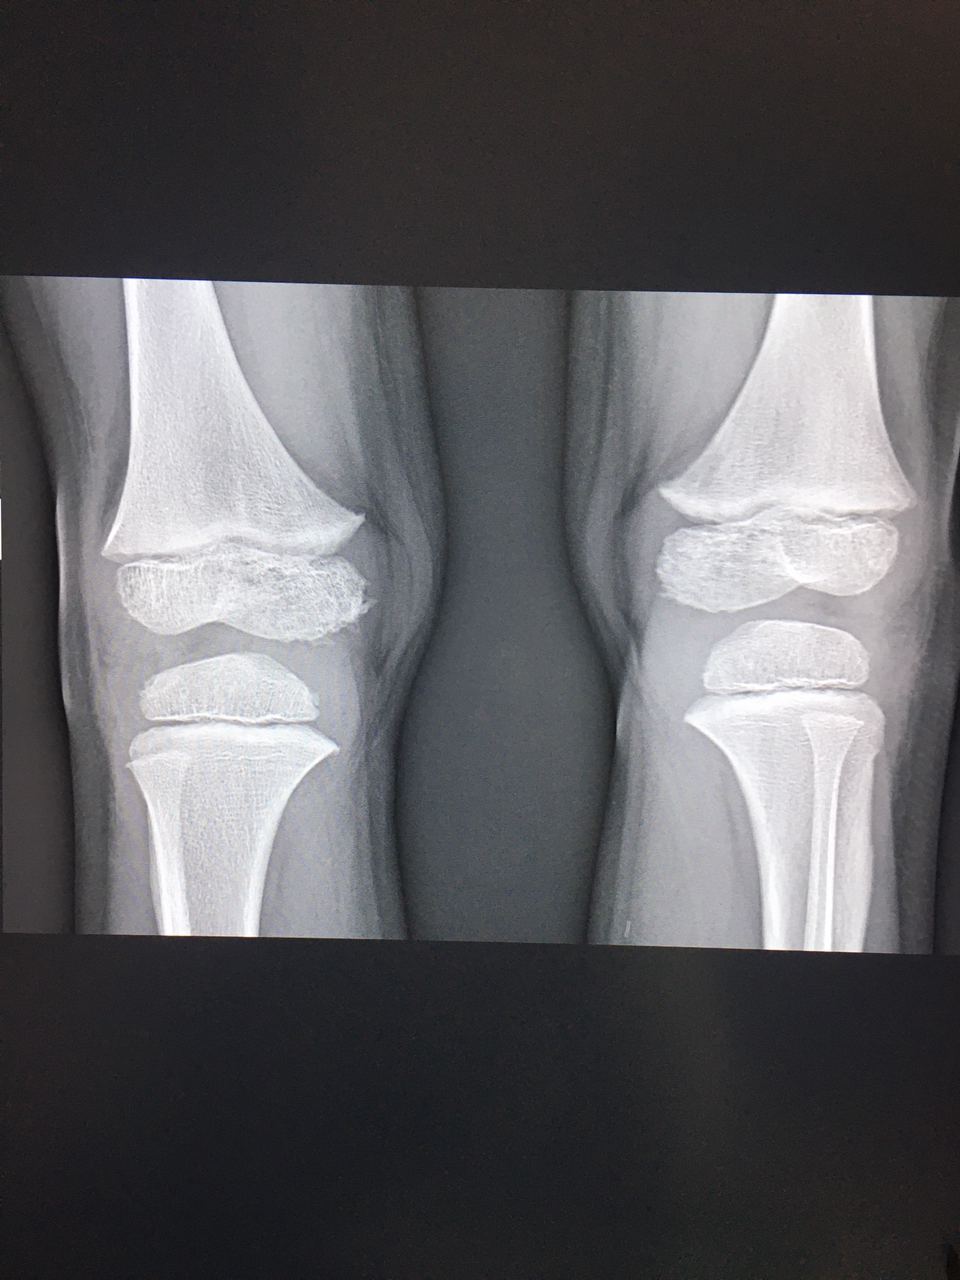

Таня Тимонина... in Radiology/Рентгенология Чатоид

Мальчик 5 лет, в направлении артралгии. Помогите описать, пожалуйста, ещё детей ни разу не описывала 🙏🏻

Таня Тимонина

Без костно-травматических. Нормальные детские колени.